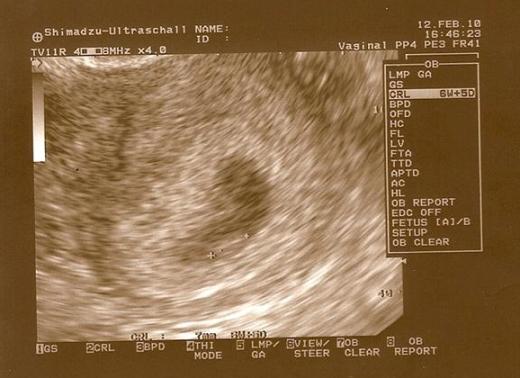

Ogolnie musze juz leciec do szpitala ale chcialam szybko wkleic wam najnowsza foteczke mojego bobaska!

8 tydzien i 2 dni :tak: Widac juz raczki i nozki :-D

• skanuj0002 (Small).jpg

skanuj0002 (Small).jpg

32,2 KB · Wyświetleń: 146

:) był pęcherzyk, echo zarodka i bijące serce:) Z CRL wychodzi równe 7 tygodni, moim zdaniem ciąża jest kilka dni starsza, ale w poprzedniej też mi pokazywało młodszą:)